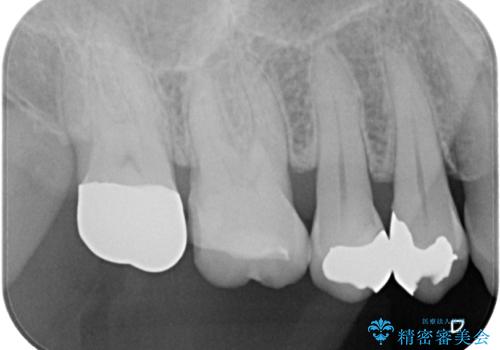

- 詰め物が欠けたとのことで来院された患者様です。来院時痛みはなく、食べ物が詰まる不快感がある状況でした。詰め物の範囲が大きくセラミックの被せもの(オールセラミッククラウン)での治療をご提案しましたが、患者様が歯はあまり削りたくないとのことで、リスクなどを説明したうえでセラミックの詰め物(ハイブリッドインレー修復)で治療していくことになりました。

拡大鏡視野下で、保険のプラスチック、虫歯の除去を行い、ハイブリッドインレーに適した形に整えました。